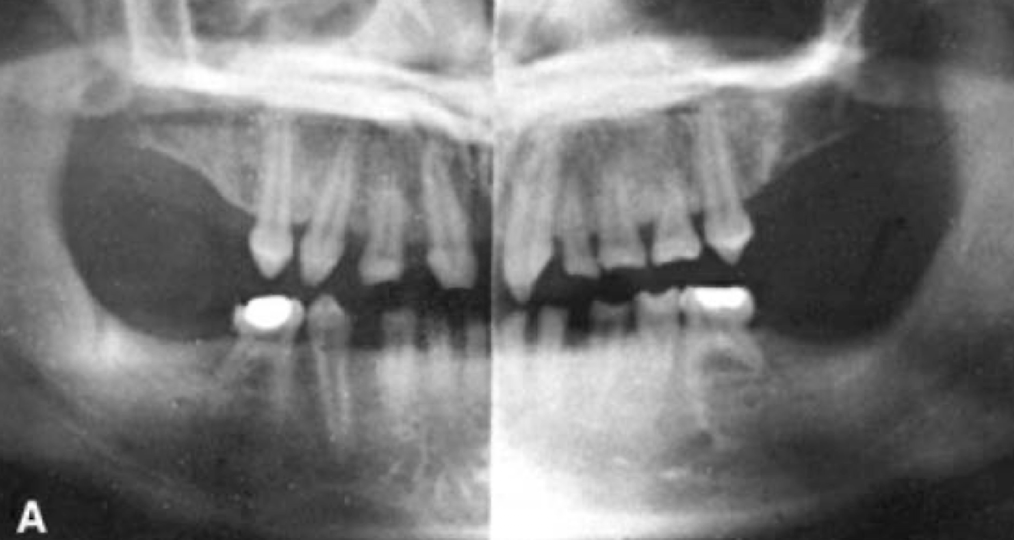

Is this x-ray, what teeth are missing?

Maxillary lateral incisors

What condition does this patient have that results in missing teeth?

Ectodermal dysplasia